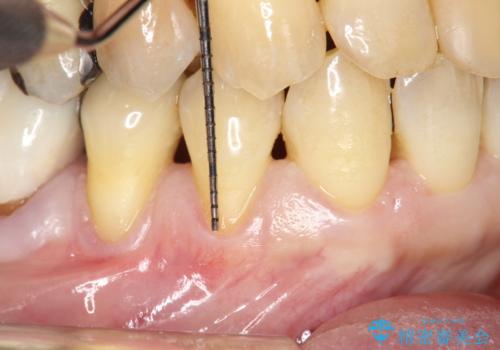

今回のケースでは小臼歯2本分の幅に渡って丈夫な歯肉を確保させるため、オペのデザイン上、横に幅広く均一な結合組織を採取する必要がありました。そのため、トラップドア方式で内部の組織をえぐって採取する術式は使わず、上顎歯肉の表層から結合組織部までを含む部分までを遊離歯肉採取の要領でやや深めに採取し、表層部分をトリミングする事で均一な厚みの結合組織を採取しました。この術式の利点として、上顎の歯肉に過度に深い侵襲を与える事がないため、組織採取部の術後の治癒が非常に早く、術後の不快症状も少なくて済む事が挙げられます。

術後3ヶ月にて意図した通りに丈夫な歯肉の幅が増大し、厚みも十分に確保できました。